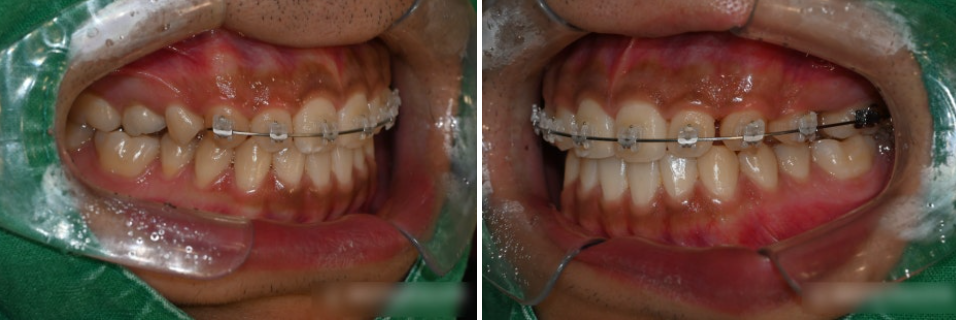

부분 교정을 진행하는 과정에서는

어금니 뿐만 아니라 다소 틀어진 앞니까지

함께 포함하여 이동시켰습니다.

꼭 치료가 필요한 치아들에만 브라켓을 부착하여

불편함을 최소로 하고 배열하던 모습입니다.

상봉동 교정치과 의 치료가 마무리가 되는 시기에

임플란트의 나사를 식립하는

방향으로 치료계획을 세웠습니다.

중간에 엑스레이 촬영으로

치아들의 반응을 살펴주며

안전하게 배열했습니다.